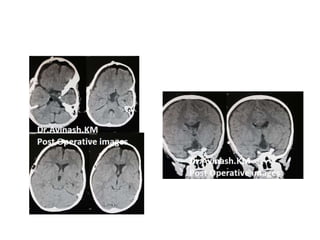

FIGURE 4. The capsule of the cystic craniopharyngioma was firmly attached to the left

hypothalamus, the stalk was dislocated to the right side (Patient 6). The outgrowth of the

craniopharyngioma from proximal stalk is recognizable A. Complete removal of the capsule was

possible, but produced subpial blood injection over the left hypothalamic surface B. MRI scan

revealed a small ischemic injury in the left hypothalamus C. This patient had transient sleep

disorder, moderate hyperphagia and memory problems (see also a supplemented video

material 1).